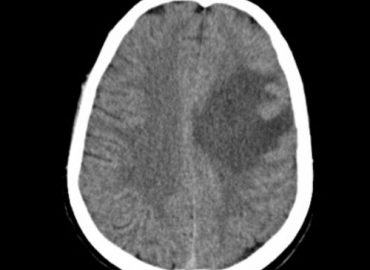

Paciente masculino de 47 años con antecedente de trasplante renal. Consulta a la guardia refiriendo cefalea de 48 hs de […]

Paciente masculino de 47 años, cursando infección por SARS CoV-2, presenta afasia mixta y disartria

70 años. Cefalea